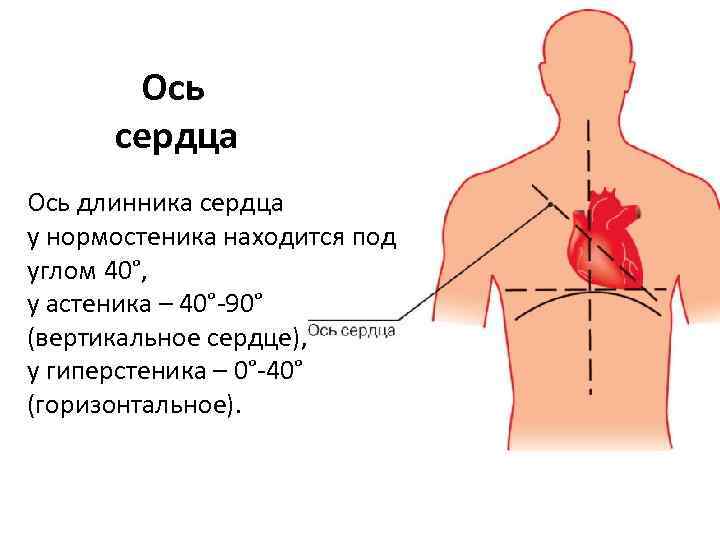

Расположение сердца у человека.

Анатомическое расположение сердца.

Где расположено сердце у человека анатомия.